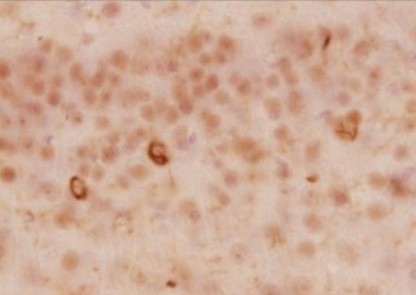

免疫組織染色

| 動物種 | ヒト (レビー小体型認知症患者) |

| 部位 | 脳 |

<データ提供>

東京大学大学院 医学系研究科 岩坪先生